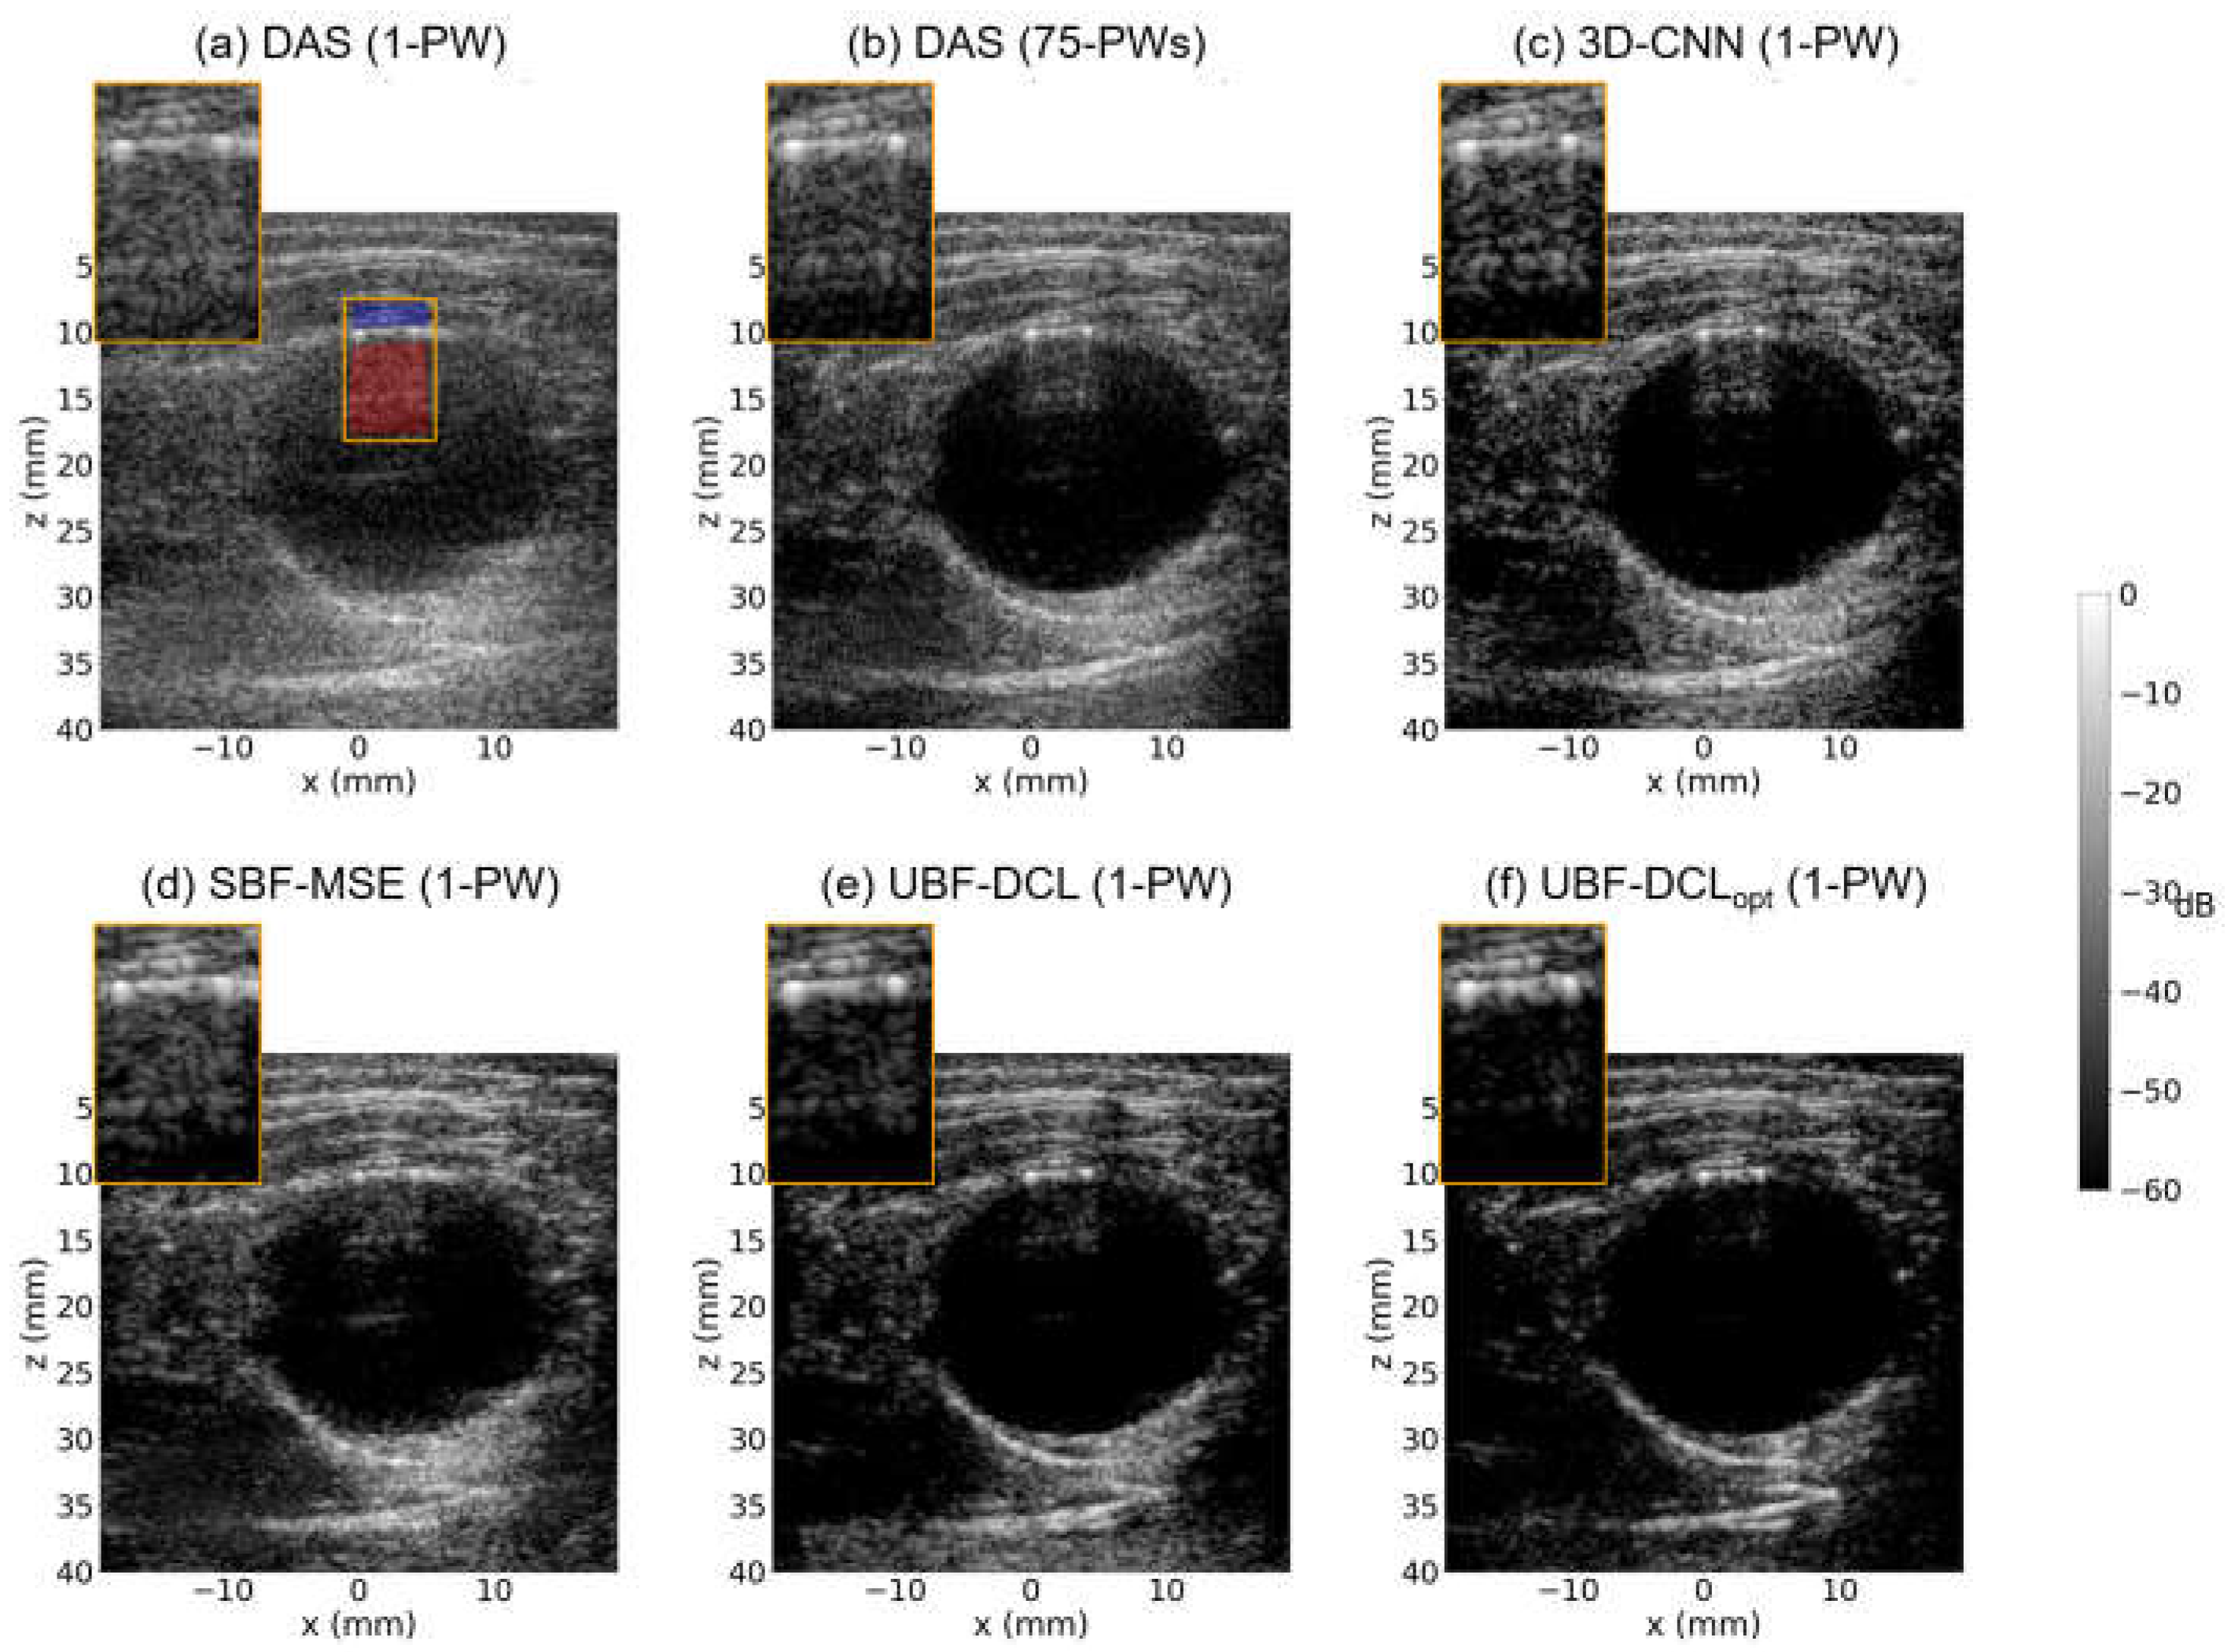

Figure 5. Reconstructed B-mode images using (a) DAS (1-PW), (b) DAS (75-PWs), (c) 3-D CNN (1-PW), (d) SBF-MSE (1-PW), (e) UBF-DCL (1-PW), and (f) UBF-DCLopt (1-PW) in the longitudinal view of the ex vivo clutter artifact phantom (D = 15 mm). The red and blue areas in the ROI were employed for CNR and gCNR measurement.

Figure 5 represents B-mode results reconstructed by 6-comparison methods, i.e., DAS with 1-PW, DAS with 75-PWs (coherent compounding), 3-D CNN with 1-PW, SBF-MSE with 1-PW, UBF-DCL with 1-PW, and UBF-DCLopt with 1-PW, respectively, in the longitudinal view of the tissue-mimicking ex vivo clutter artifact phantom with the diameter of 15 mm. As illustrated in Figure 5a, reverberation artifacts were successfully generated in the DAS (1 PW) image along the longitudinal wall, resembling an in vivo arterial vessel. In addition, severe reverberation was observed in the orange ROI region due to its low image quality. Figure 5b shows the reconstructed DAS (75 PWs) image, where severe reverberation artifacts are still present, although the image quality was substantially improved by using 75 PW transmissions and the coherent compounding technique. The 3-D CNN method based on supervised learning achieved moderate clutter suppression with relatively high image quality; however, residual clutter artifacts were still observed in the ROI region, as depicted in Figure 5c. Figure 5d shows the SBF-MSE result using MSE loss with 75-angle DAS as ground truth. While this method achieved improved image quality compared to DAS (1 PW) and 3-D CNN, some residual artifacts remain visible in the ROI region. Figure 5e presents the UBF-DCL based on unsupervised learning and it demonstrated superior clutter suppression performance compared to DAS (75 PWs), despite requiring only a single PW transmission. In contrast, as shown in Figure 5f, the proposed UBF-DCLopt demonstrated the most effective clutter suppression performance among the five approaches, eliminating most of the reverberation artifacts observed in the ROI region.

The second row of Table 2 summarizes the measured CNR and gCNR values for all six comparison methods in the longitudinal view of the ex vivo clutter artifact phantom (D = 15 mm). The red and blue areas in the ROI (Figure 5a) were used for CNR and gCNR measurement. The DAS (75 PWs) method exhibited higher CNR and gCNR values than DAS (1 PW), 3-D CNN (1 PW), and SBF-MSE (1-PW) methods. However, the UBF-DCL method outperformed DAS (75 PWs) in both CNR and gCNR measurements despite its much higher temporal resolution. This unsupervised learning–based method also achieved higher CNR and gCNR values than both 3-D CNN and SBF-MSE methods based on supervised learning. The proposed UBF-DCLopt yielded the highest CNR and gCNR values among all six comparison methods. In addition, the optimized coherence loss based unsupervised beamforming (UBF-DCLopt) yielded about 16% improvement compared to the general unsupervised beamforming using general coherence loss (UBF-DCL).